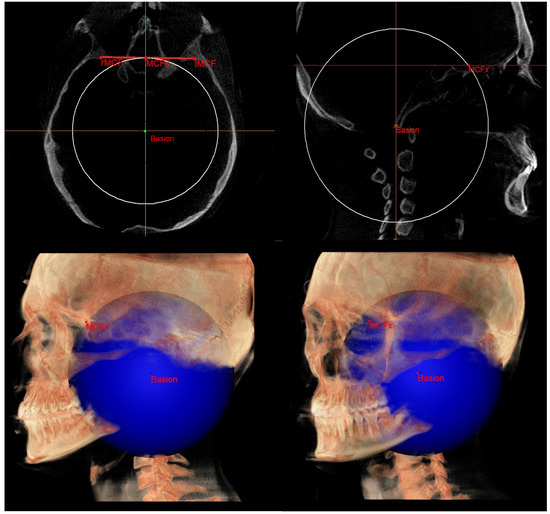

- PM (Figure 4) was identified by the points lMCF, rMCF and posterior nasal spine (PNS);

| Basion (Ba) | Most anterior point of foramen magnum | Most anterior point of foramen magnum | Most anterior point of foramen magnum |

| Middle point MCF (MCFx) | / | Point of intersection between the plane on which the Ba lies and a line joining the left and right MCF | / |

| MCF neutral (MCFn) | Plane passing through the Ba, rSEn and lSEn which forms an angle of 40.3° with the PMn at the SEn point |

| Construction plane through Ba (CPBa) | Construction plane passing through Ba and parallel to the PM |